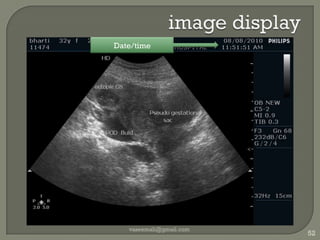

image displayvaseemali@gmail.com52Date/time

image displayvaseemali@gmail.com53Clinic info

image displayvaseemali@gmail.com54Patient  info